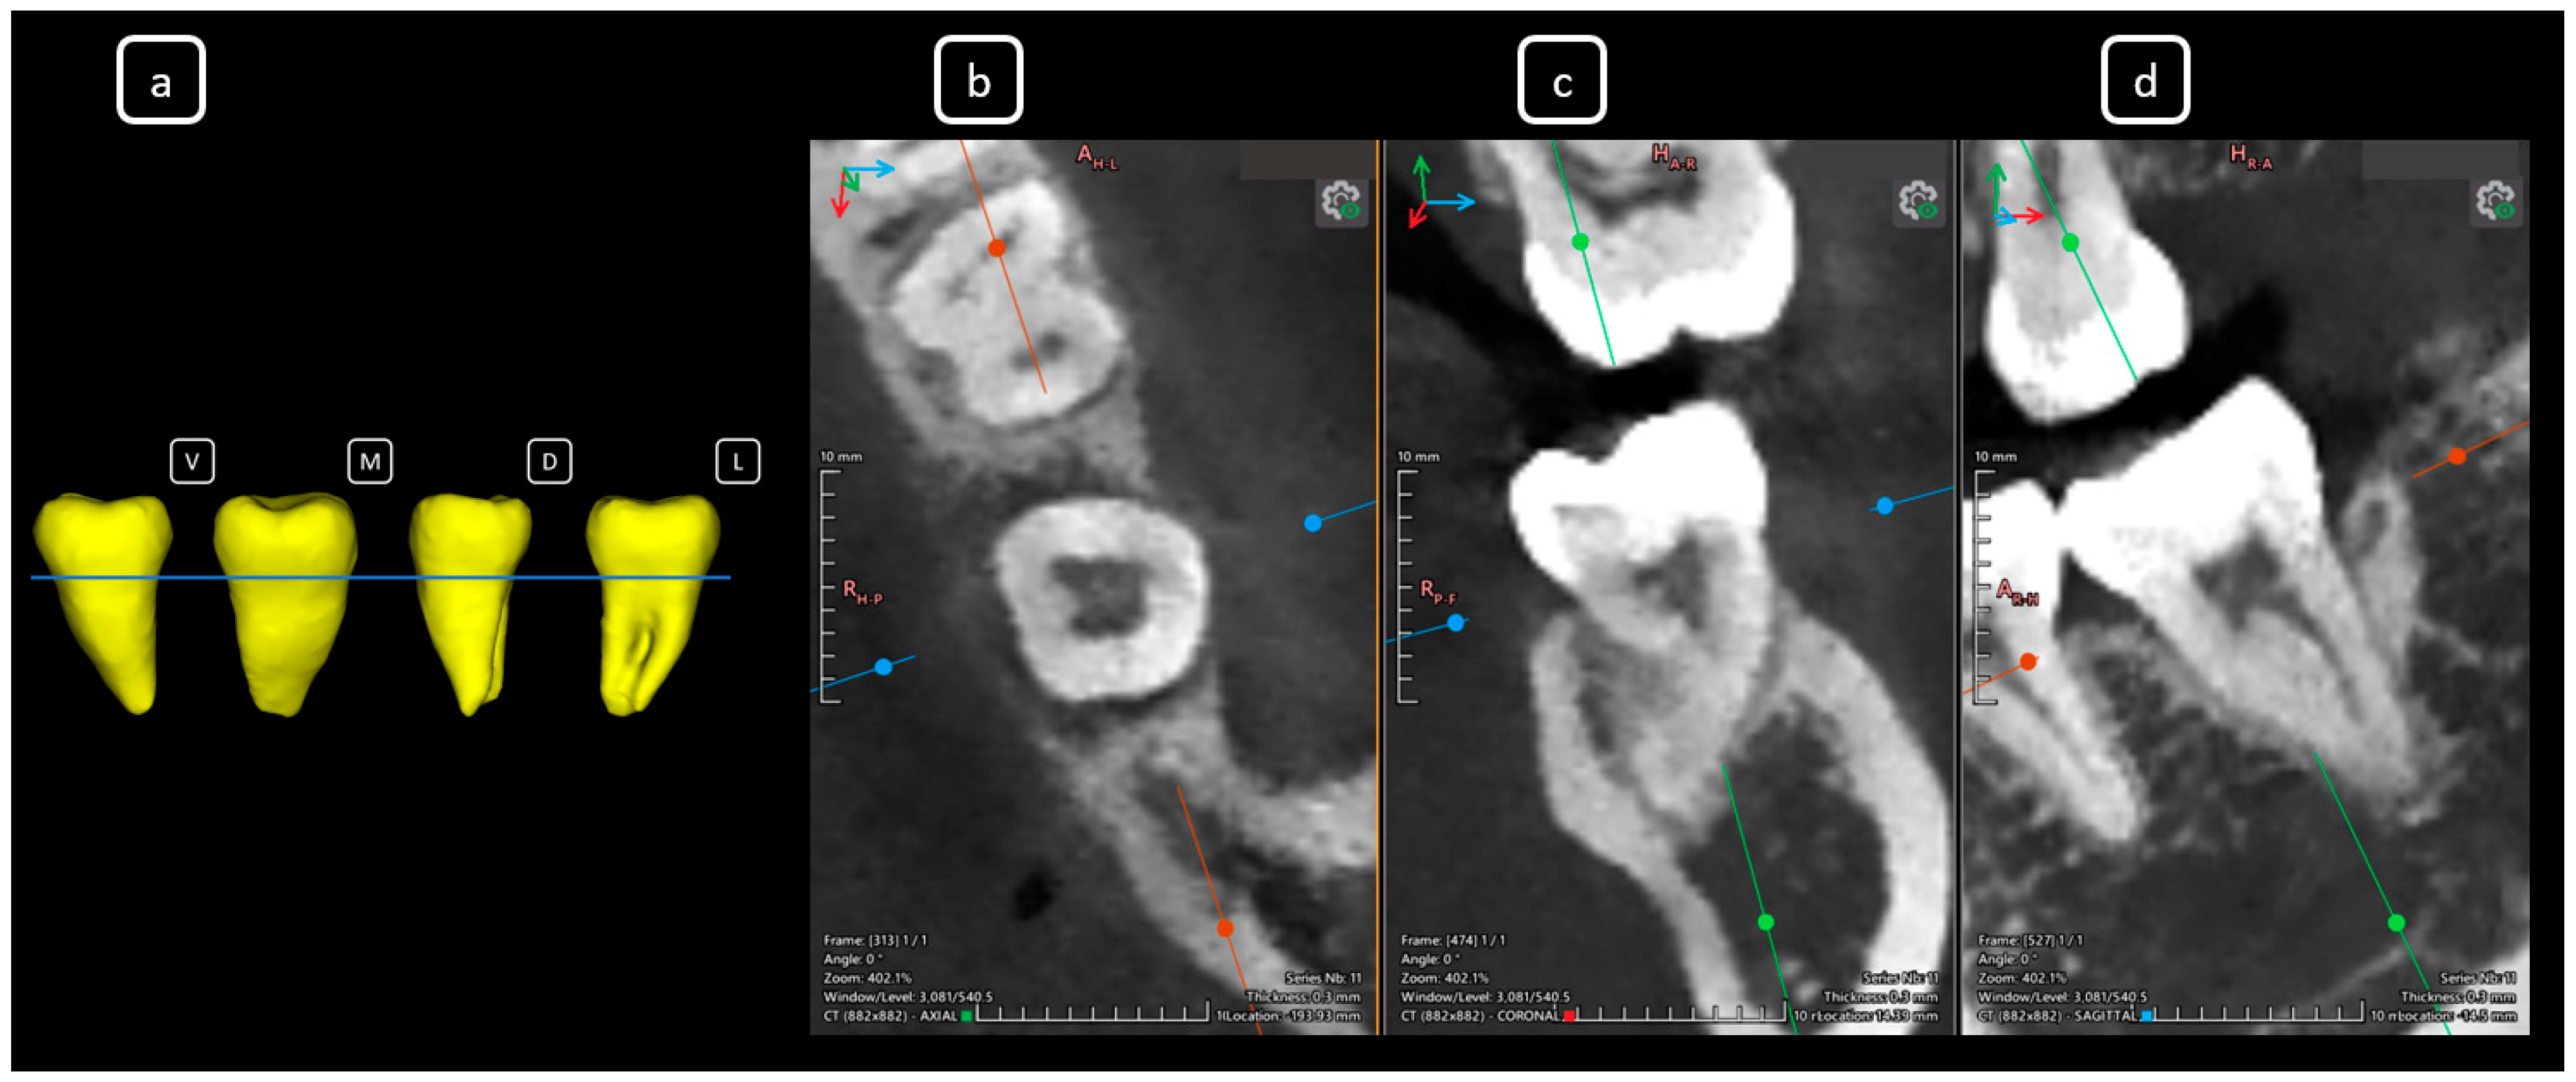

Imaging Findings of Clinical Significance in Endodontics During Cone Beam Computed Tomography Scanning of the Upper Airway—The Anterior, Bilateral, C-Shaped, Dual of Mandibular Root Canals: A Brief Case Report

García-Torres, E.; Guerrero-Falcón, D.L.G.; Bojórquez-Armenta, H.A.; Almeda-Ojeda, O.E.; Barajas-Pérez, V.H.; Solís-Martínez, L.J. Imaging Findings of Clinical Significance in Endodontics During Cone Beam Computed Tomography Scanning of the Upper Airway—The Anterior, Bilateral, C-Shaped, Dual of Mandibular Root Canals: A Brief Case Report. Diagnostics 2025, 15, 3157. https://doi.org/10.3390/diagnostics15243157